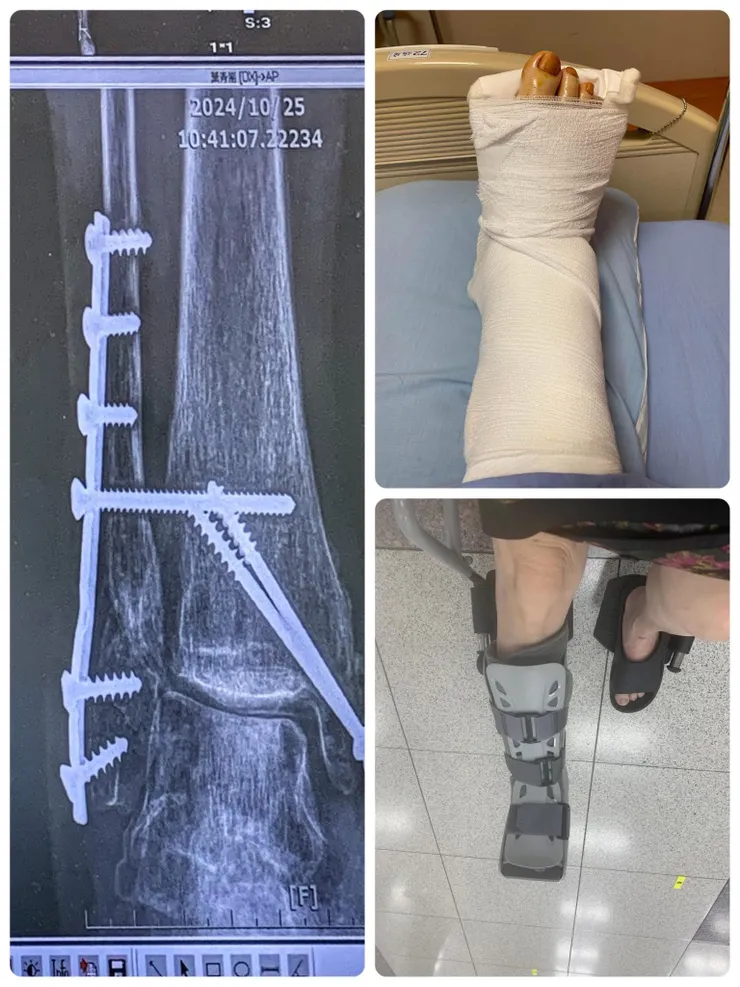

左邊是已經打上一支鋼片和兩隻鋼釘的X光片。右上是2024年7月30日經過5個半小時手術被推進病房時。右下是術後2024年9月26日試穿護具鞋。